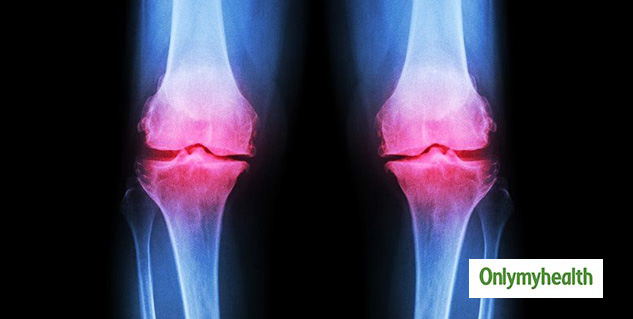

अध्ययन के मुताबिक, घुटने का ऑस्टियोअर्थराइटिस दर्दभरा होता है, जिस स्थिति से विश्वभर में लाखों लोग प्रभावित हो रहे हैं। इस स्थिति के कारण लोगों को ज्वांइट फेल्योर और असमिति दर्द झेलना पड़ता है।

शोधकर्ताओं ने एक ऐसी दवा की पहचान की है, जो ऑस्टियोअर्थराइटिस में हड्डियों और कार्टिलेज के बढ़ने को महत्वपूर्ण रूप से रोक सकती है। जर्नल एनाल्स ऑफ इंटरनल मेडिसिन में प्रकाशित एक अध्ययन में शोधकर्ताओं ने पाया कि 'एमआईवी-711' ऑस्टियोअर्थराइटिस में बीमारी के बढ़ने को रोक सकती है। 'एमआईवी-711' एक तरह का कैथेप्सिन के प्रावरोधक (cathepsin K inhibitor) है। हालांकि अध्ययन में इस बात पर भी विशेष रूप से जोर दिया गया है कि ये दवा घुटने के ऑस्टियोअर्थराइटिस से संबंधित दर्द को कम करने के लिए प्लेसिबो के मुकाबले ज्यादा प्रभावी नहीं है।